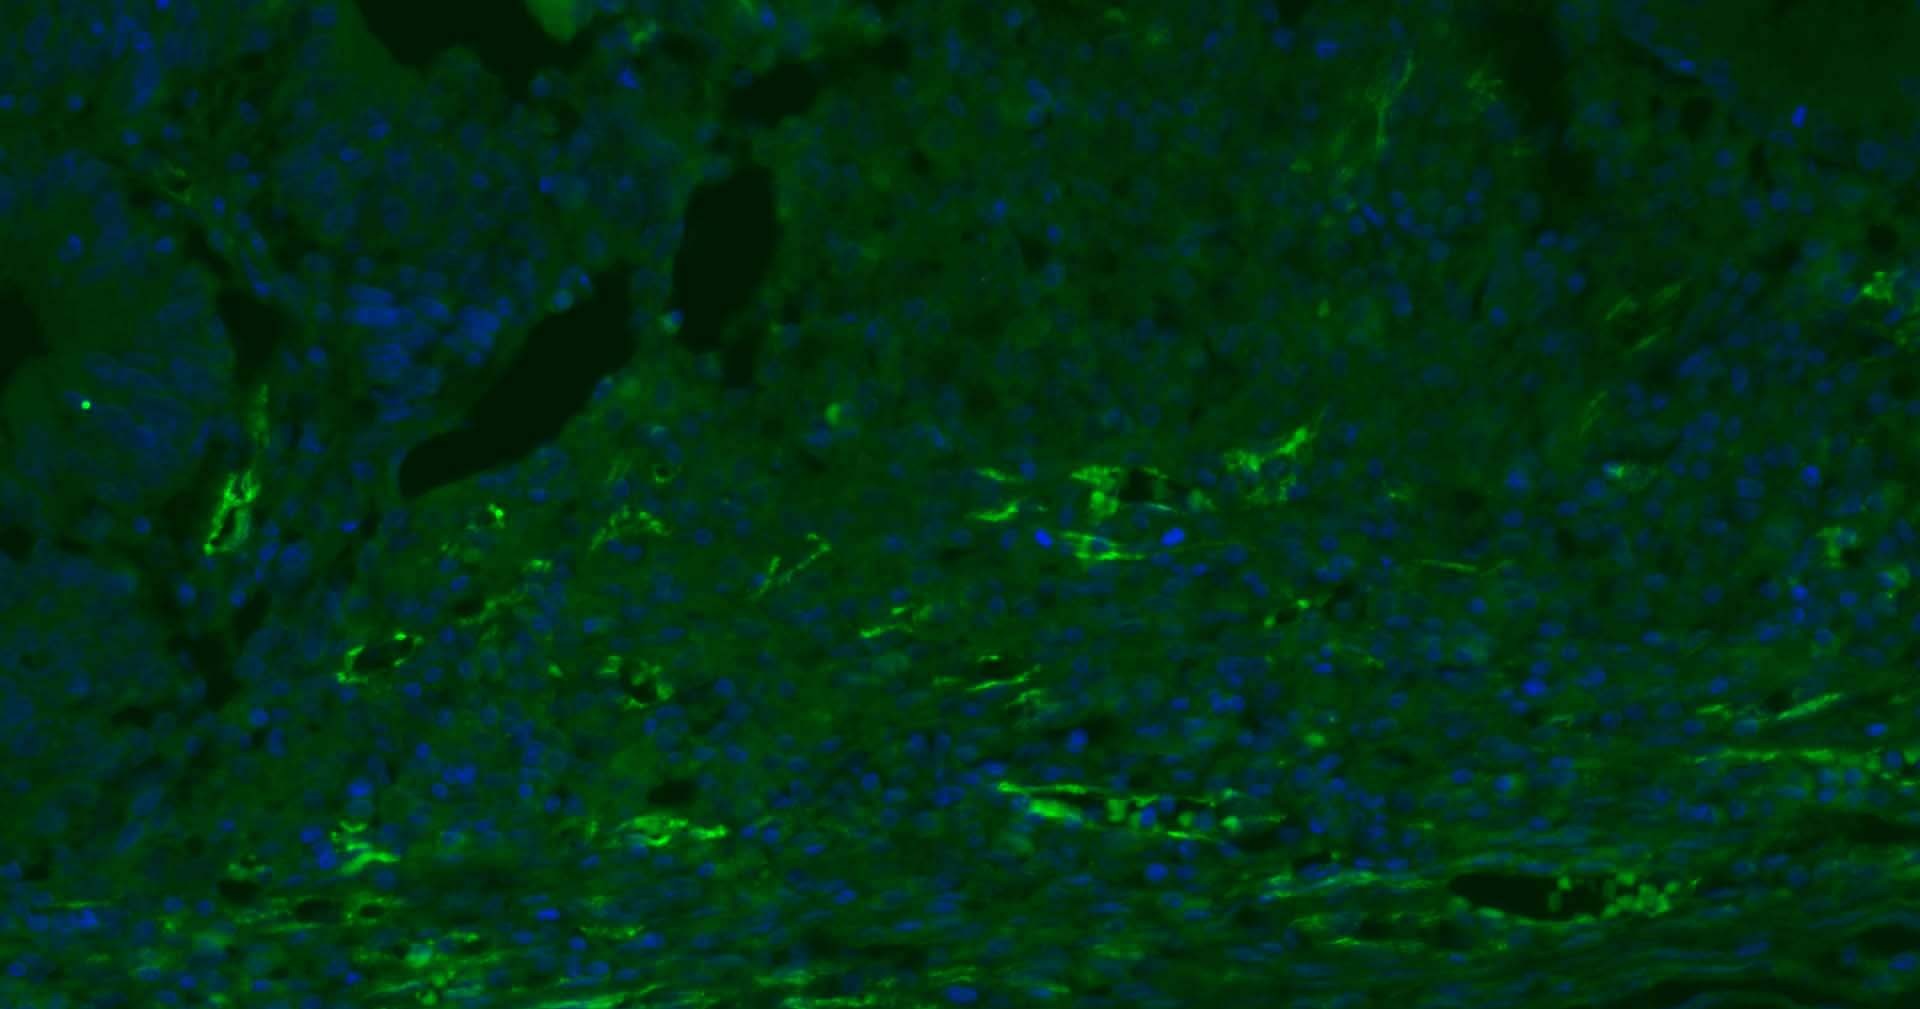

3. Paraformaldehyde-fixed, paraffin embedded Human Tonsil; Antigen retrieval by boiling in sodium citrate buffer (pH6.0) for 15 min; Antibody incubation with CD31 Monoclonal Antibody, Unconjugated (TMAB-00354) at 1:200 overnight at 4°C. Followed by conjugated Goat Anti-Rabbit IgG antibody (green), DAPI (blue) was used to stain the cell nucleus.

4. Paraformaldehyde-fixed, paraffin embedded Human Liver; Antigen retrieval by boiling in sodium citrate buffer (pH6.0) for 15 min; Antibody incubation with CD31 Monoclonal Antibody, Unconjugated (TMAB-00354) at 1:200 overnight at 4°C. Followed by conjugated Goat Anti-Rabbit IgG antibody (green), DAPI (blue) was used to stain the cell nucleus.